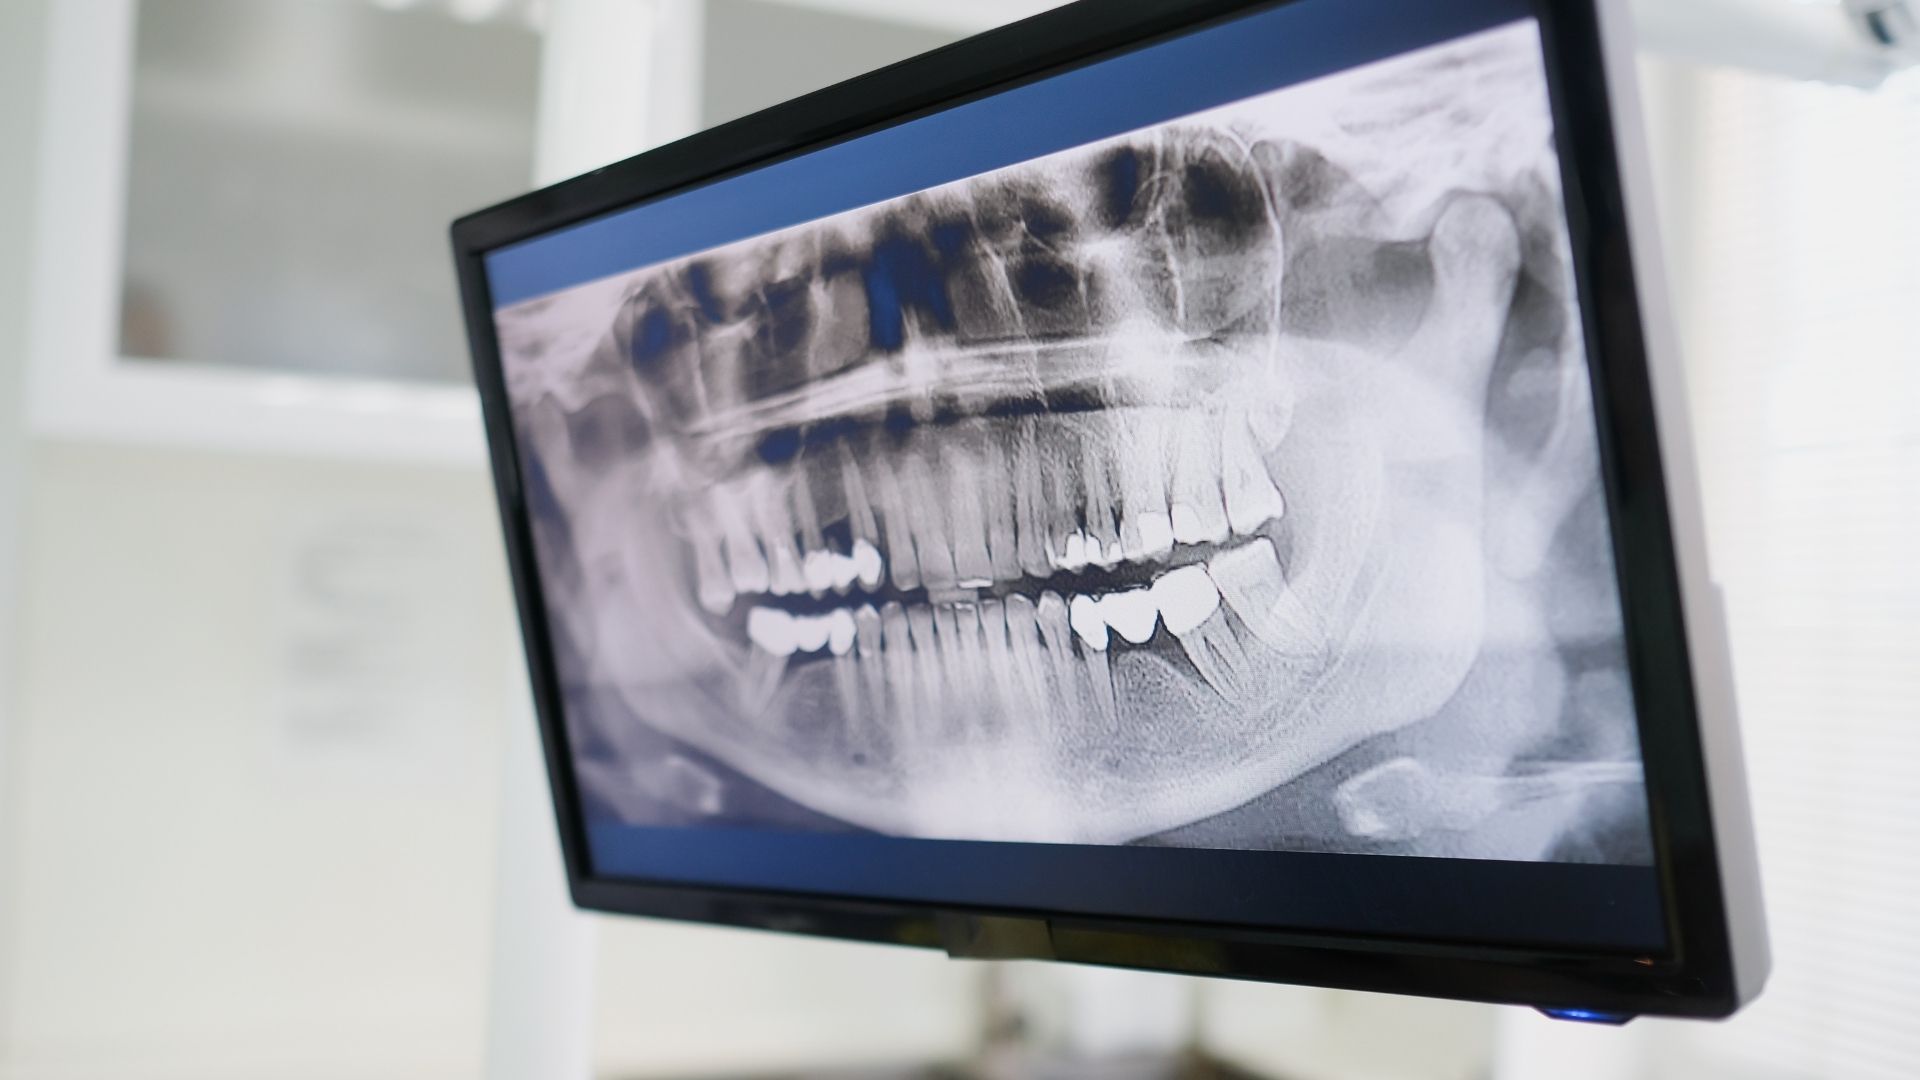

- Chụp X-quang khớp hàm: Phát hiện tổn thương khớp, lệch khớp hoặc tiêu xương quanh răng.